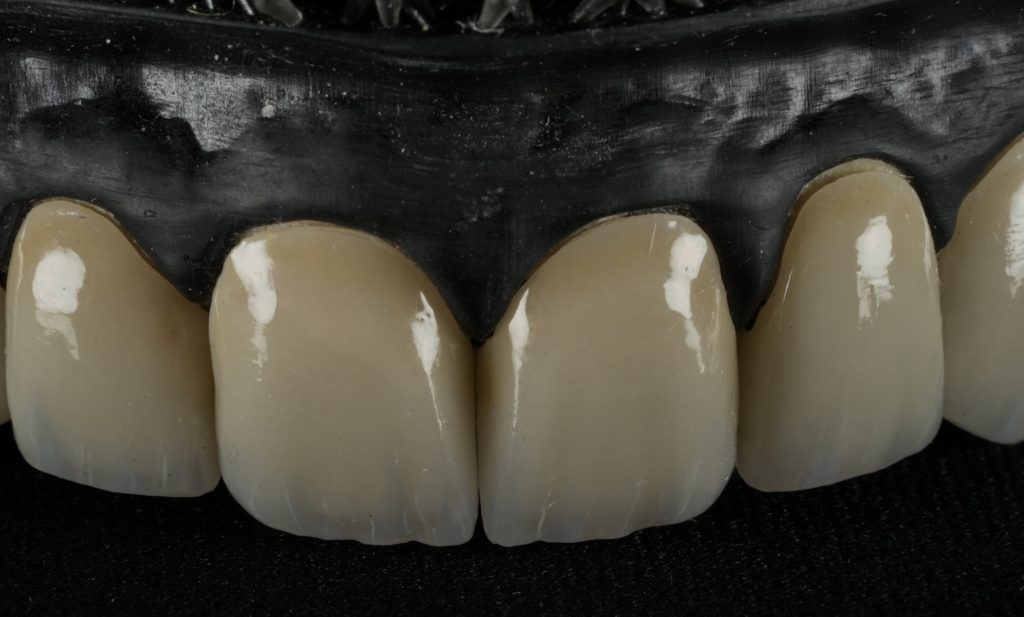

Margins were refined using fine diamond strips, and surface gloss was enhanced with a multi-step polishing system (Shofu OneGloss + OptraPol Next Gen). Post-operative evaluation showed ideal incisal translucency, line-angle symmetry, and gingival health (Fig 5 & 6).